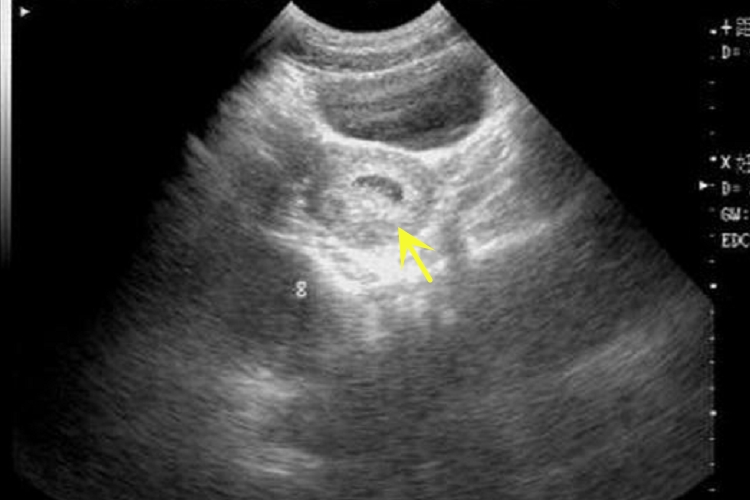

一个月左右的孕囊,一般指怀孕4-5周的孕囊,此时的孕囊的形态可为直径1-2cm的圆形或椭圆形的囊状结构。但大部分人群无法在此阶段通过B超检查观察到孕囊,小部分人群可以经B超在宫腔内看到孕囊,为宫底部较高回声的环状影。